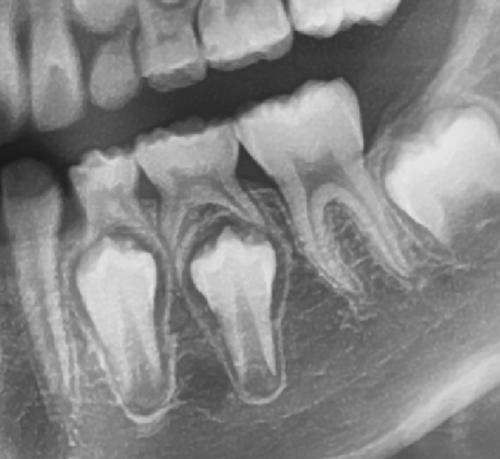

흔들리는 치아는 꼭 뽑아야 할까?

안녕하세요 목동안치과 안상우 원장입니다.오늘은 치아가 흔들리게 된다면 뽑아야만 하는것인지에 대해서 한번 알아 보려고 해요.치아가 흔들리는 증상에 대해 이해하기 위해서는 치주조직에 대한 이해가 우선필요합니다.치아는 잇몸뼈에 고정이 되어 교합압을 담당하게 됩니다잇몸뼈와 치조골 사이에는 치주인대라고 하는 치아를 고정시켜주는 조직이 있습니다. 이 조직에 유격이 발생하거나 하면 치아가 흔들리게 되는거에요.사진과 같이 치아뿌리 주변에는 치조골이 있고 이 치조골을 치주인대가 감싸고 있습니다.치아 뿌리 주변에 하얗게 보이는 것이 치밀화된 골인데요 이 골에 치주인대가 치아 뿌리와 연결되어 치아를 지지하는 역활을 하게 되요.치아가 흔들리는것은 치아에 가해지는 힘과 이 치주인대가 버텨주는 힘이 잘 균형을 이루냐에 있습니다.자 그럼 흔들리는 치아는 뽑아야만 할까요?결론적으로 그렇지 않습니다.치아가 흔들려도 통증과 염증이 없고 정상적으로 교합을 한다면 계속해서 사용할수 있어요.치아가 흔들리는 여러 상황을 한번 가정해 볼께요일단 정상 치주조직에서의 상황입니다.정상적인 치주조직으로 지지되는 치아에 각각의 교합력이 걸렸을경우를 가정해 볼께요 약한힘이나 중간힘까지는 치주가 버텨줄수 있습니다.하지만 너무 강한 힘이 작용하게 되면 치주조직에 손상이 와서 치아가 흔들릴수 있어요.반면 잇몸뼈가 내려간 상황을 한번 볼께요이런 치주조직에서는 가해지는 힘이 약한경우에는 치아가 정상적인 기능을 하게 됩니다하지만 중간정도에 힘에서는 치아가 흔들리게 되고 통증이 생길수도 있어요.강한힘에는 아마도 치아가 탈락을 하겠죠치아가 흔들리거나 해도 치주조직에 염증이 없고 통증이 없으며 치아가 정상적으로 기능을 한다면 계속 사용할수 있어요.흔들리며 통증을 유발하는 치아가 있다면 다음 세가지 경우에 따라서 치료나 관리를 해야 합니다첫번째는 흔들리는 치아 주변에 잇몸에 염증이 있는 경우 입니다.염증은 약한 잇몸을 더 망가뜨릴수 있습니다.염증을 유발하는 치석이 있다면 스케일링이나 잇몸치료를 해야합니다.잇몸에 염증이 생기지 않도록 칫솔과 치실 그리고 치간칫솔로 잘 관리해줘야 해요.두번째로는 치주조직이 버티기 힘든 힘이 치아에 가해졌을 경우입니다.이런경우에는 치아에 가해지는 교합력을 줄이거나 교합간섭을 조정해 줘야 합니다.마지막으로 치아를 잡아 주는 치조골 자체가 염증으로 인해서 완전히 망가져서 치주인대가 존재하지 않는 경우입니다.사진과 같이 잇몸위에 완전히 떠있는 경우를 생각할수 있습니다.이런상태는 이미 몸이 치아를 외부물질로 인식하고 있는것입니다.우리몸에 가시가 박히면 아프고 주변으로 염증이 생기잖아요?몸에 밖힌 가시가 우리의몸과 하나가 되지 않듯이 이미 몸에서 치아를 밀어내고 있는것이기 때문에 이런경우에는 안타깝지만 발치를 해야 해요.발치를 하고 나면 해당부위에 임플란트나 보철치료를 해야 할수 있습니다.어떻셨나요? 치아가 흔들린다면 당황해 하지 마시고 치과에서 진료를 받아보세요.치아가 흔들리는 원인과 치주상태를 평가한다음 관리를 해서 사용할수 있도록 해보세요.